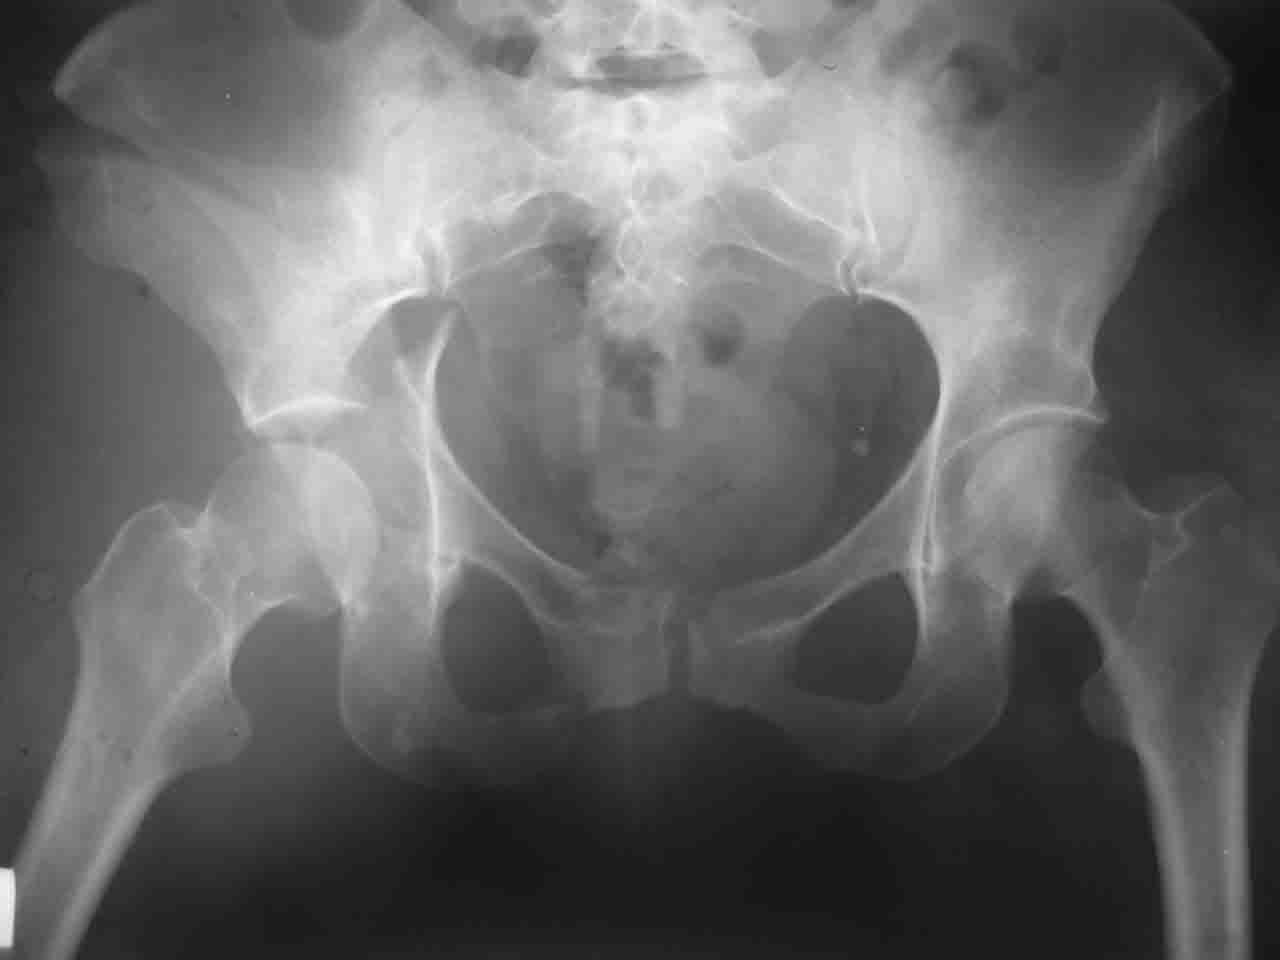

Re: Перелом вертлужной впадины

Смирнов Алексей 09 Ноябрь 2004, 01:17

Снимки и схема